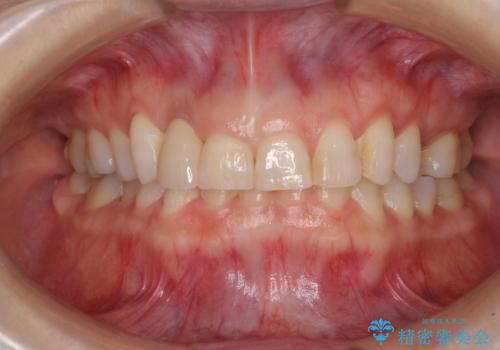

仮歯に置き換えた際に歯周外科処置を行い、歯肉の腫脹が落ち着いたことを確認してオールセラミッククラウンにて補綴することとしました。

外科処置後の痛みを気にしていましたが、小規模の処置であったため、痛みを感じることはほとんどありませんでした。

気になっていた腫脹がなくなり、患者様には大変満足していただきました。